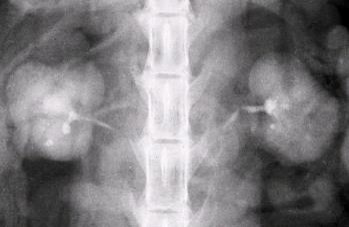

What are these and what is the significance?

Renal coritcal cysts

Fluid filed cavities.

You will see one or two cysts in the cortex! Often incidental. If you have many cysts e.g. polycystic kidney dx – reduce the amount of functional tissue = problems